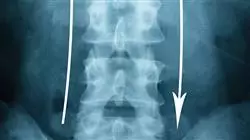

1.1.1. Изображение при торако-поясничных и крестцовых переломах

1.1.1.3. Управление и использование радиологической визуализации

1.1.1.4. Определить показания для соответствующего использования КТ или МРТ

1.1.2.2. Различать классификации Denis, AO и TLICS

1.5.1.1. Переломы позвонков с неврологическим поражением. Биомеханика. Критерии стабильности. Средства диагностики

1.5.1.2. Отличительная визуализационная диагностика травмы позвонков с неврологическим поражением